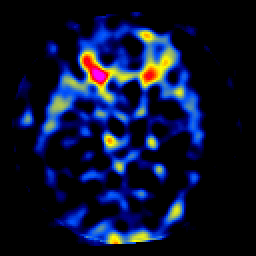

SPECT TL Study #7 -- Slice #23